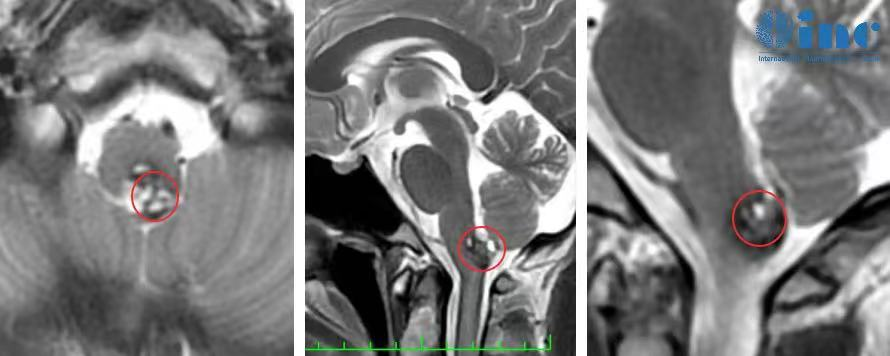

患者阿朔,19岁男性,大学生,确诊为脑干延髓海绵状血管瘤。发病前身体状况良好,热爱生活,具有积极向上的精神状态。疾病确诊时,医疗团队告知手术存在术后瘫痪和生活不能自理的风险,患者及家属陷入深度焦虑。

疾病最严重阶段,患者出现明显呼吸障碍症状,因氧气供应不足导致站立不稳。初期症状被家属误判为感冒或普通身体不适,建议通过服药休息缓解。随着症状加剧,患者主动要求就医检查,影像学检查显示脑内存在异常病灶,最终确诊为脑干海绵状血管瘤。

手术于2022年11月27日实施,全程进行手术直播。术中在神经电生理监测下,巴特朗菲教授成功完成肿瘤全切手术,操作精准有序。患者术后苏醒迅速,在ICU期间即恢复基本沟通能力,能够使用手机与家人联系。